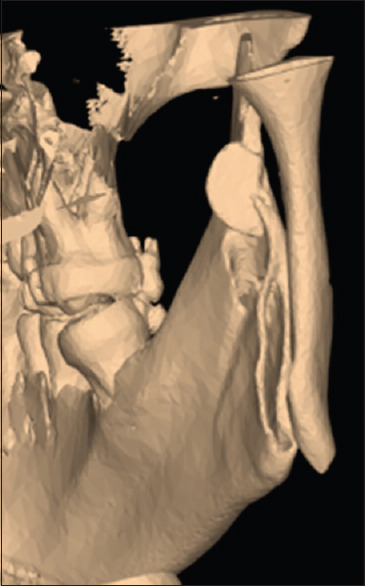

Diagnosis: Postoperative Computed Tomography (CT) images showed the broken blade embedded in the upper part of the right vertical ramus osteotomy.

Outcome: The broken saw was pushed laterally from the medial aspect of the ramus using a periosteal elevator and retrieved from the lateral aspect of the mandible with curved haemostatic forceps without complications.